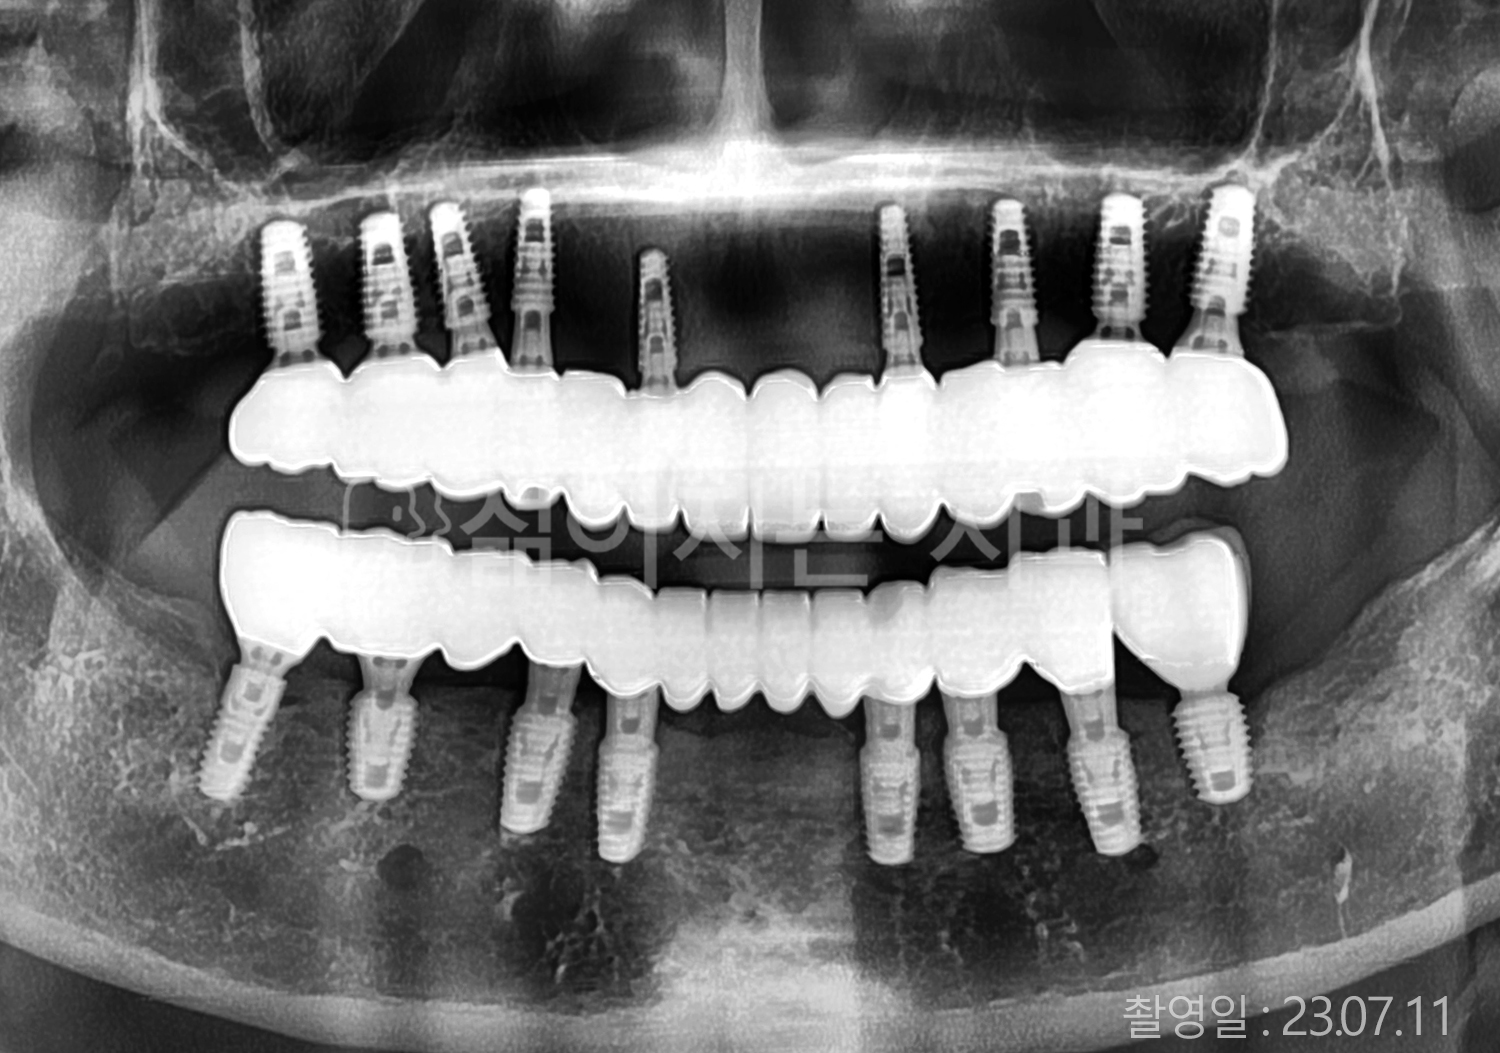

• 70대 고혈압, 고지혈증 전체치아 10개 이상 임플란트

• 60대 당뇨, 간염 전체치아 10개 이상 임플란트

• 80대 골다골증 전체치아 6개 이상 임플란트

• 70대 고혈압, 당뇨 전체치아 10개 이상 임플란트

• 60대 간 질환 전체치아 10개 이상 임플란트

• 60대 전체치아 10개 이상 임플란트